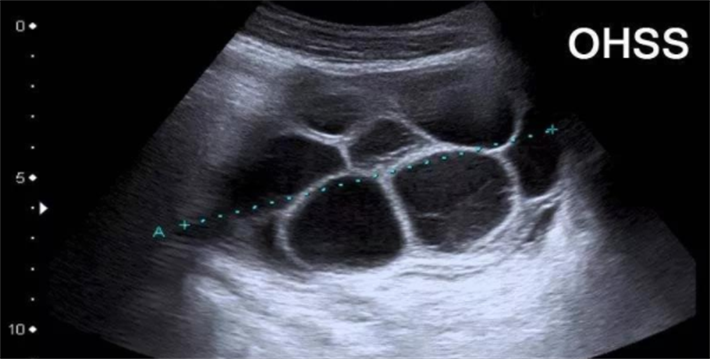

OHSS是一种人体对促排卵药物产生过度反应的医源性疾病,在试管婴儿治疗中并不罕见。其主要症状包括卵巢增大、腹水、胸水、血液浓缩、电解质紊乱、肝肾功能损害,甚至可能出现血栓形成等严重并发症,对女性的健康乃至生命安全构成威胁。

在试管周期中,高获卵数往往被视为成功的关键因素之一。更多的卵子意味着有更多机会形成优质胚胎,从而提高妊娠成功率。对于那些卵巢储备功能下降或存在其他生育障碍的女性来说,获取足够数量的卵子尤为重要。但这并不意味着获卵数越多越好,当获卵数过多时,女性发生卵巢过度刺激综合征(OHSS)的风险也会显著增加。